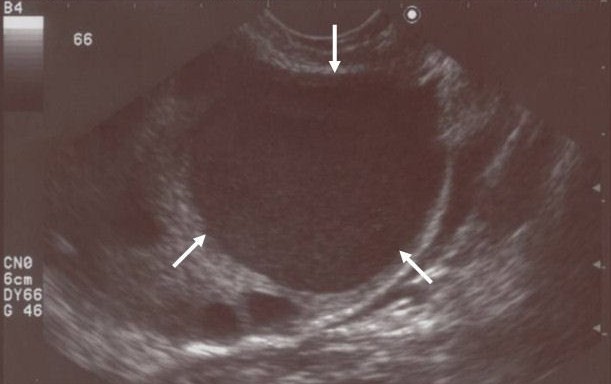

L'echographie est effectuée en général d'abord par voie abdominale (sonde sur le ventre ), puis par voie vaginale (une sonde plus petite est introduite dans le vagin ). le radiologue ou le gynecologue peut ainsi repérer la taille du kyste, le coté ou il se trouve, l'aspect de la paroi du kyste. C'est l'examen de référence ! Cet examen est sans danger pour l'organisme, le résultat est immédiat, et indolore pour le patient. Pour une echographie abdominale, on vous demandera de boire un peu d'avant l'examen. Si vous devez subir ensuite l'echographie par voie vaginale, on vous fera alors vider votre vessie.